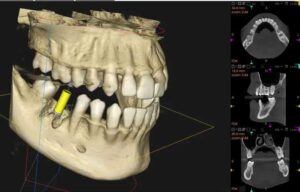

インプラント治療

インプラント治療においては、インプラント体を埋入する際に顎骨の高さ、幅、密度を詳細に把握する必要があるため、歯科用CT検査が基本的に必須です。

レントゲンでは骨の幅を確認することができないため、歯科用CTによる三次元的な評価が不可欠となっています。

歯科用CT画像により神経管の位置を三次元的に把握することで、リスクの少ない埋入位置と深さを計画することができます。

また、歯科用CTデータを用いたコンピューターシミュレーションにより、適したインプラントの位置、角度などを術前に決定することも可能となります。